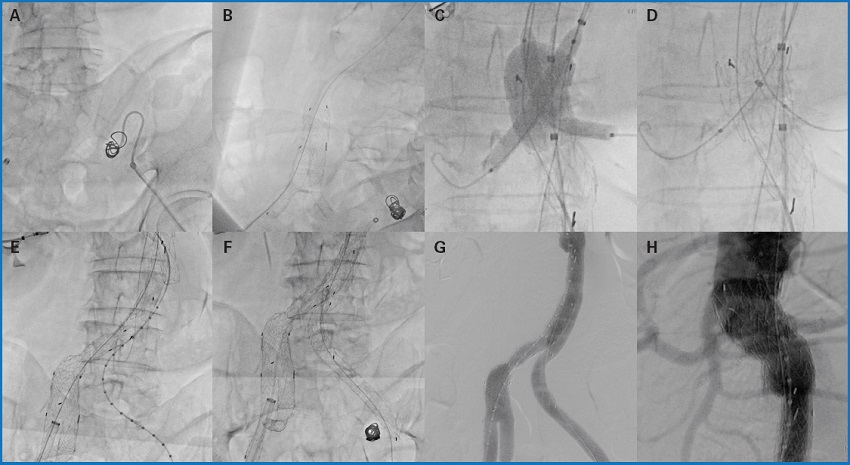

PROCEDIMIENTO TÉCNICO (Fig. 2)

Figura 2. Procedimiento técnico. A. Embolización hipogástrica izquierda. B. Despliegue de branch ilíaco derecho. C-D. Despliegue de stents renales y de endoprótesis aortobiilíaca. E. Colocación de pata puente derecha. F. Colocación de pata izquierda. G-H. Resultado angiográfico final.

Se comienza el procedimiento con punción ecoguiada retrógrada de ambas arterias femorales comunes y colocación de introductores de 5 Fr. Se dejan colocados cierres percutáneos de tipo Proglide® en ambas regiones inguinales (dos en cada una). Heparinización sistémica con 7500 unidades. Por la ingle izquierda se canaliza la arteria hipogástrica izquierda mediante catéter Simmons® y se realiza su embolización con coils Azur35® de 13 mm con buen resultado angiográfico. Por la ingle derecha se progresa una guía Advantage® de 0,035 y se coloca un introductor de 18 Fr. Se procede a la disección de la arteria humeral izquierda proximal. Se coloca un introductor de 10 Fr de 80 cm y se canaliza con catéter RIM® y guía Advantage® de 0,035 hasta AAA. Se realiza técnica through and through. Por la ingle derecha se coloca branch ilíaco GORE® de 23 × 12 mm. A través del through and through se coloca un introductor de 10 Fr en el branch y se canaliza la arteria hipogástrica derecha. Se coloca un stent VBX-GORE® de 8 × 79 mm, posdilatando la zona proximal con un balón de angioplastia Armada35® de 14 × 40 mm, con buen resultado morfológico. A través de la arteria humeral izquierda más distal se coloca un introductor de 8 Fr de 70 cm y se canaliza con catéter RIM® y guía Advantage® de 0,035 hasta el AAA. A través de los introductores del brazo se canalizan ambas arterias renales y se posicionan, sin desplegar, en renal derecha un stent VBX-GORE® de 8 × 59 mm y en renal izquierda, otro stent VBX-GORE® de 7 × 59 mm. A través de la ingle derecha se coloca el cuerpo de la prótesis GORE EXCLUDER® de 32 × 14 mm, enrasando en arteria mesentérica superior (AMS). Se realiza técnica kissing balloon de ambos stents renales y del cuerpo protésico. Permeabilidad de renales y AMS. Se finaliza el eje derecho con una pata puente de GORE® de 16 × 24 mm. A través del brazo se canaliza la pata contralateral y se realiza through and through con un lazo. Se colocan dos patas (16 × 14,5 mm proximal y 16 × 12 mm distal), enrasando en la arteria ilíaca externa izquierda. Muy buen resultado angiográfico sin demostrar endofugas. Cierre percutáneo de ambos accesos femorales con Proglides®. Cierre de arteria humeral izquierda con puntos de Prolene® de 6/0. Cierre por planos y de la piel con grapas.

El paciente es dado de alta al segundo día posoperatorio completamente asintomático, con presencia de pulso radial izquierdo y, a nivel de miembros inferiores, pulso pedio derecho y tibial posterior izquierdo. Durante el seguimiento el paciente permanece asintomático y se observan todos los stents permeables en los angio TC de control correspondientes.